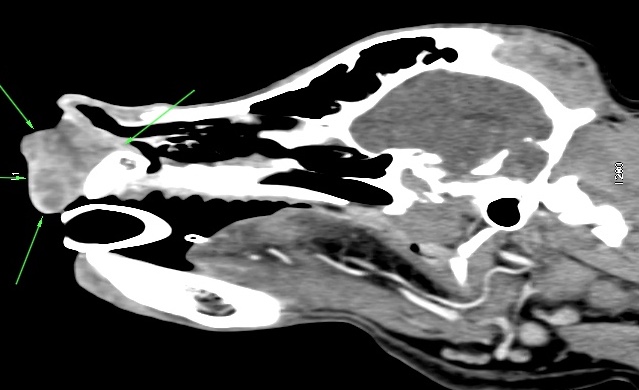

Peritumoral injection of contrast agent was then used as a type of indirect lymphography. In Cadbury’s case, the lymphatics could be traced from the tumour site to one of the submandibular lymph nodes which were therefore identified as the SLN (Figure 3). Peritumoral vital dye was then injected and Cadbury was taken to theatre where the dye had drained along the lymphatics to colour the SLN blue aiding its identification (fig 4).

Figure 3: Indirect lymphographic CT showing contrast enhancing SLN